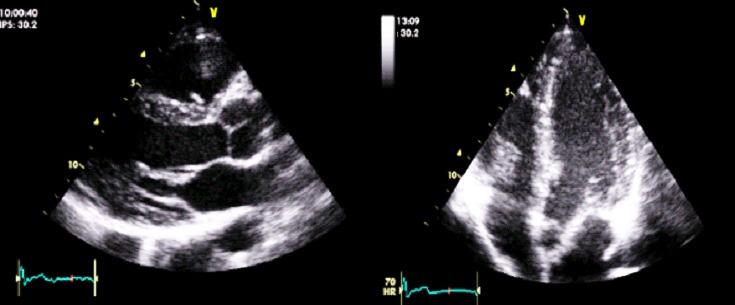

Belhassen anterior fascicular ventricular tachycardia: a case in a black African.

Belhassen ventricular tachycardia can be characterized by a complete right branch block and a right axial deviation. This type, although rare, must be recognized to properly treat the patient, as verapamil treatment is effective.